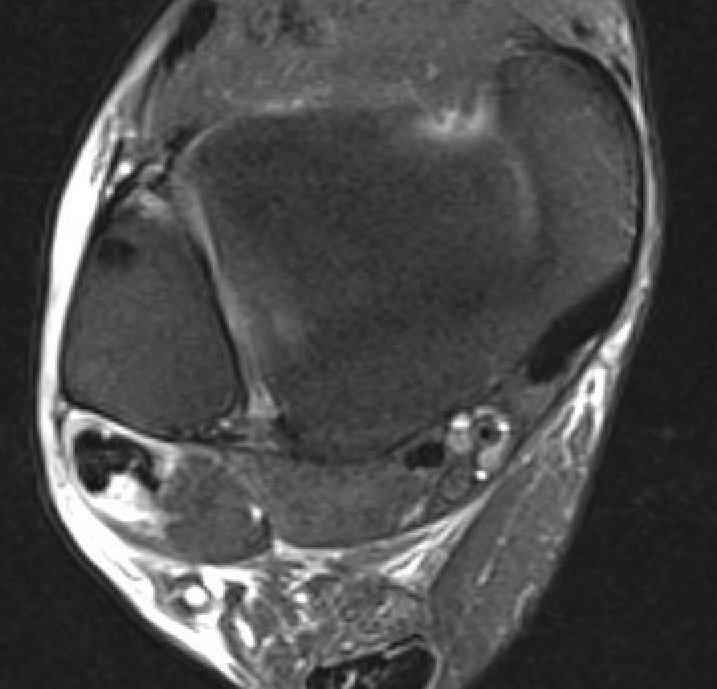

- tears

Avoid magic angle effect at ankle - parasagittal obliques / plantar flex ankle

Peroneal brevis tears